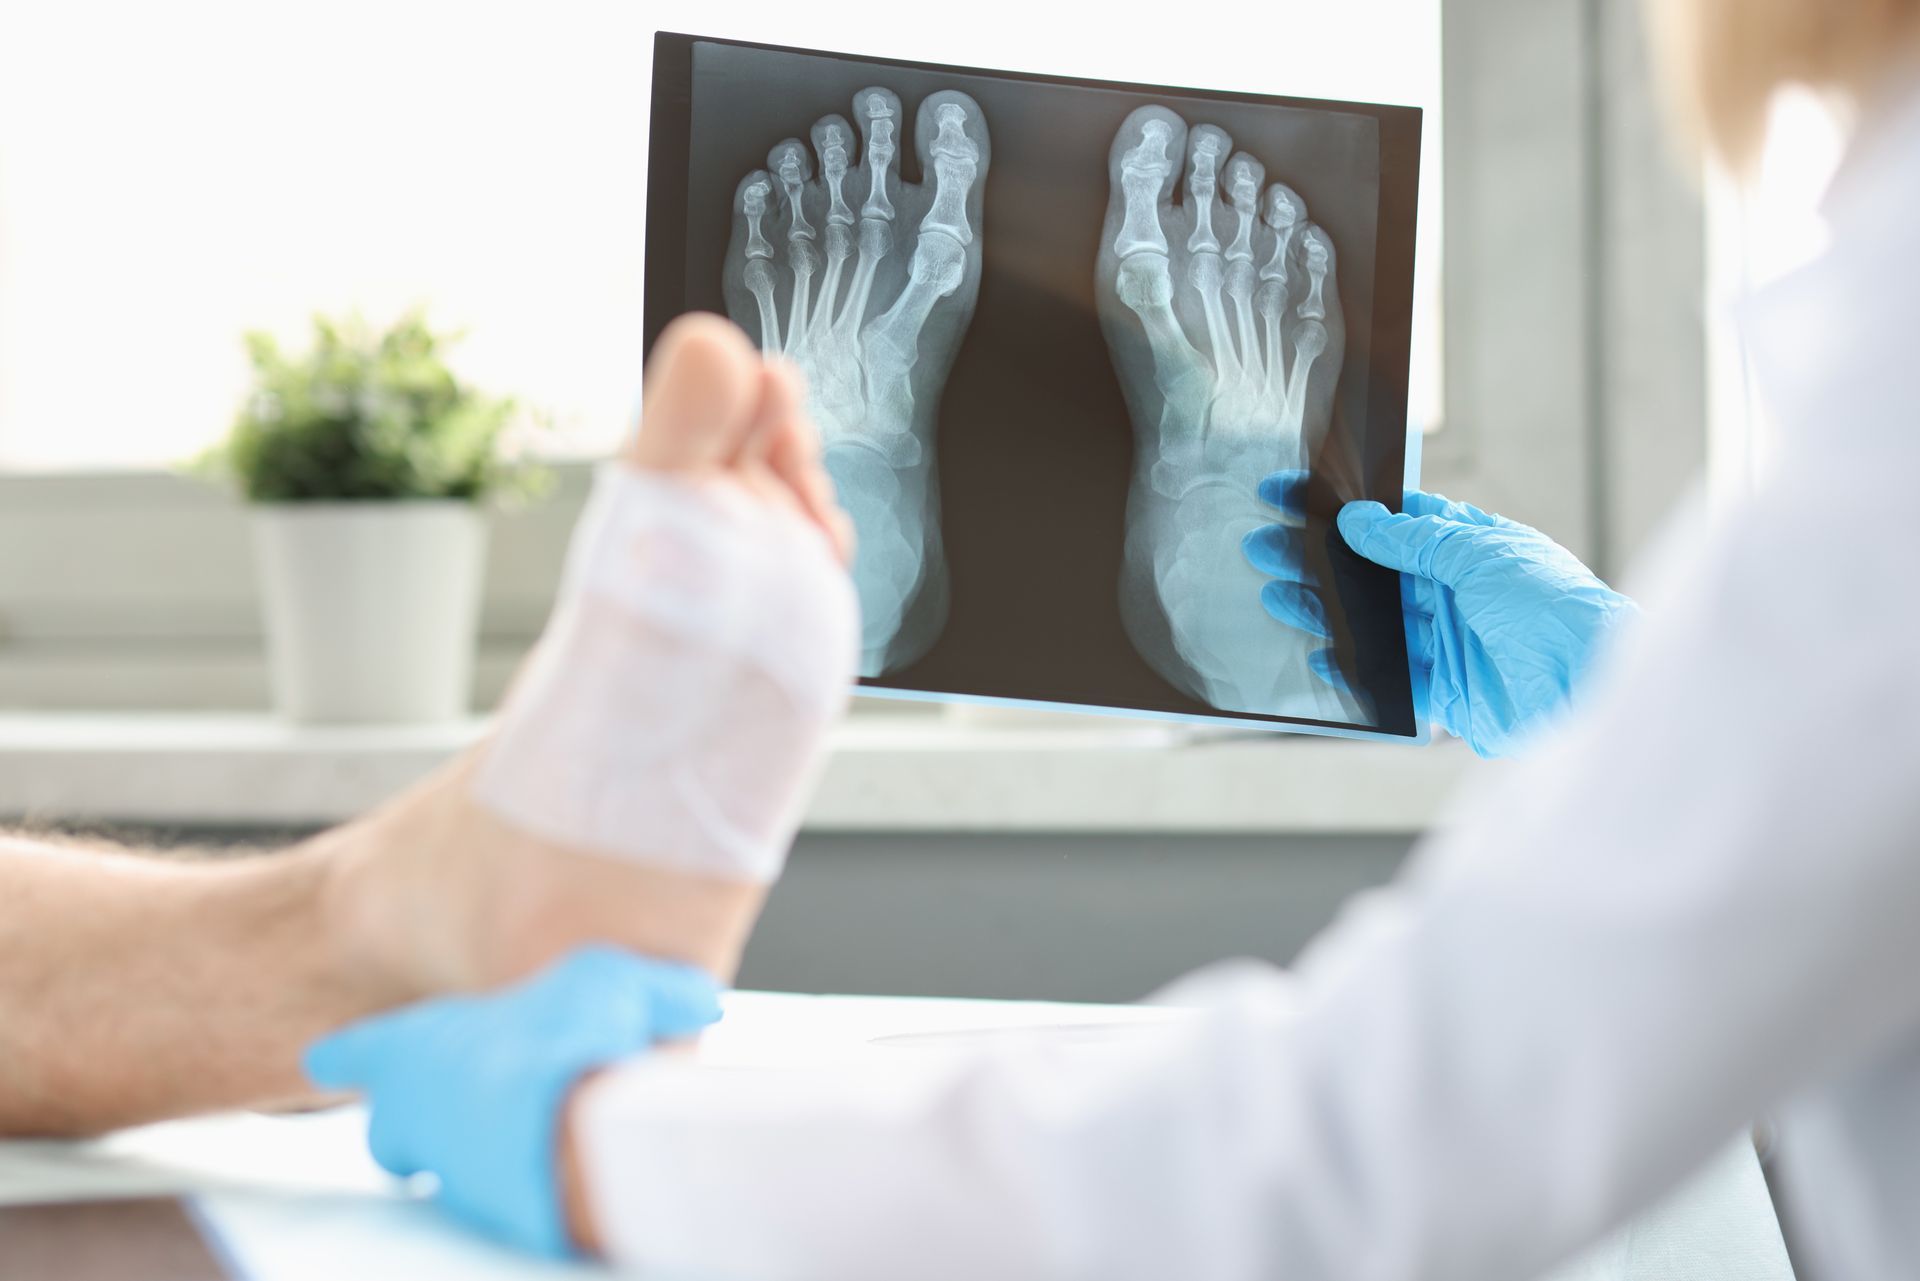

Podiatric medicine focuses on diagnosing and treating conditions of the foot, ankle, and related structures of the leg. Podiatrists perform thorough examinations, make accurate diagnoses, and provide treatments that may include medication, therapeutic exercises, custom orthotics, surgical procedures when needed, and guidance on footwear, prevention, and lifestyle habits to support long-term lower extremity health and overall well-being.